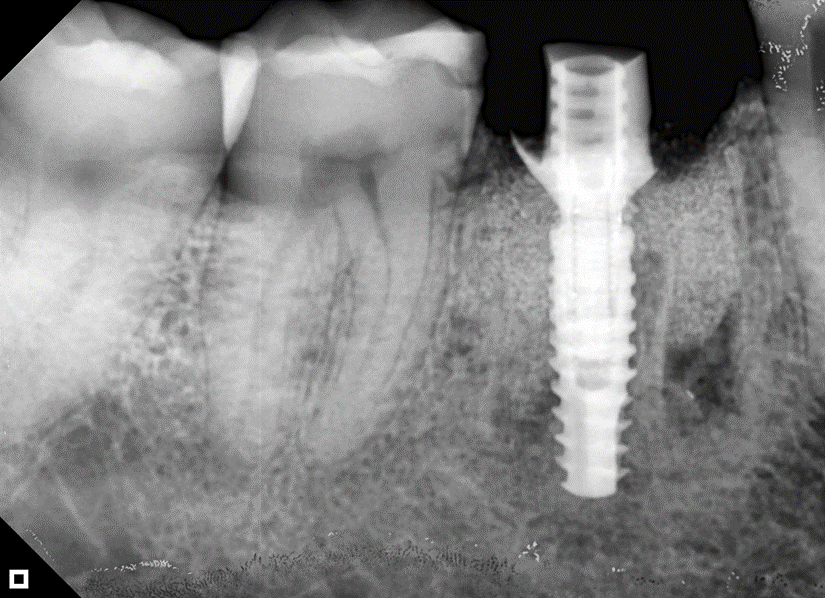

O paciente apresentou fratura vertical mésio-distal no elemento 46. Foi planejada a exodontia minimamente traumática e instalação imediata do implante Maestro Superiore (Implacil Osstem) utilizando uma guia prototipada. Após a exodontia, o implante foi instalado seguindo o protocolo de cirurgia guiada. O GAP vestibular foi preenchido com o Extra Graft. Um cicatrizador personalizado impresso com haletas facilitadoras foi capturado com resina flow e instalado. Após 30 dias, foi realizado escaneamento indireto para obtenção do perfil de emergência, utilizando protocolo digital com sobreposição do cicatrizador escaneado para confecção da coroa definitiva em zircônia policristalina estabilizada por ítria.

A reabilitação imediata de áreas posteriores com implantes instalados no alvéolo pós-extração tem mostrado alta previsibilidade, especialmente quando associada a guias cirúrgicos prototipados e componentes personalizados. O uso de implantes com conexão cônica interna, como o Maestro Superiore (Implacil Osstem), proporciona maior estabilidade mecânica e melhor vedação bacteriana na interface implante/pilar, contribuindo para a manutenção óssea marginal1,2.